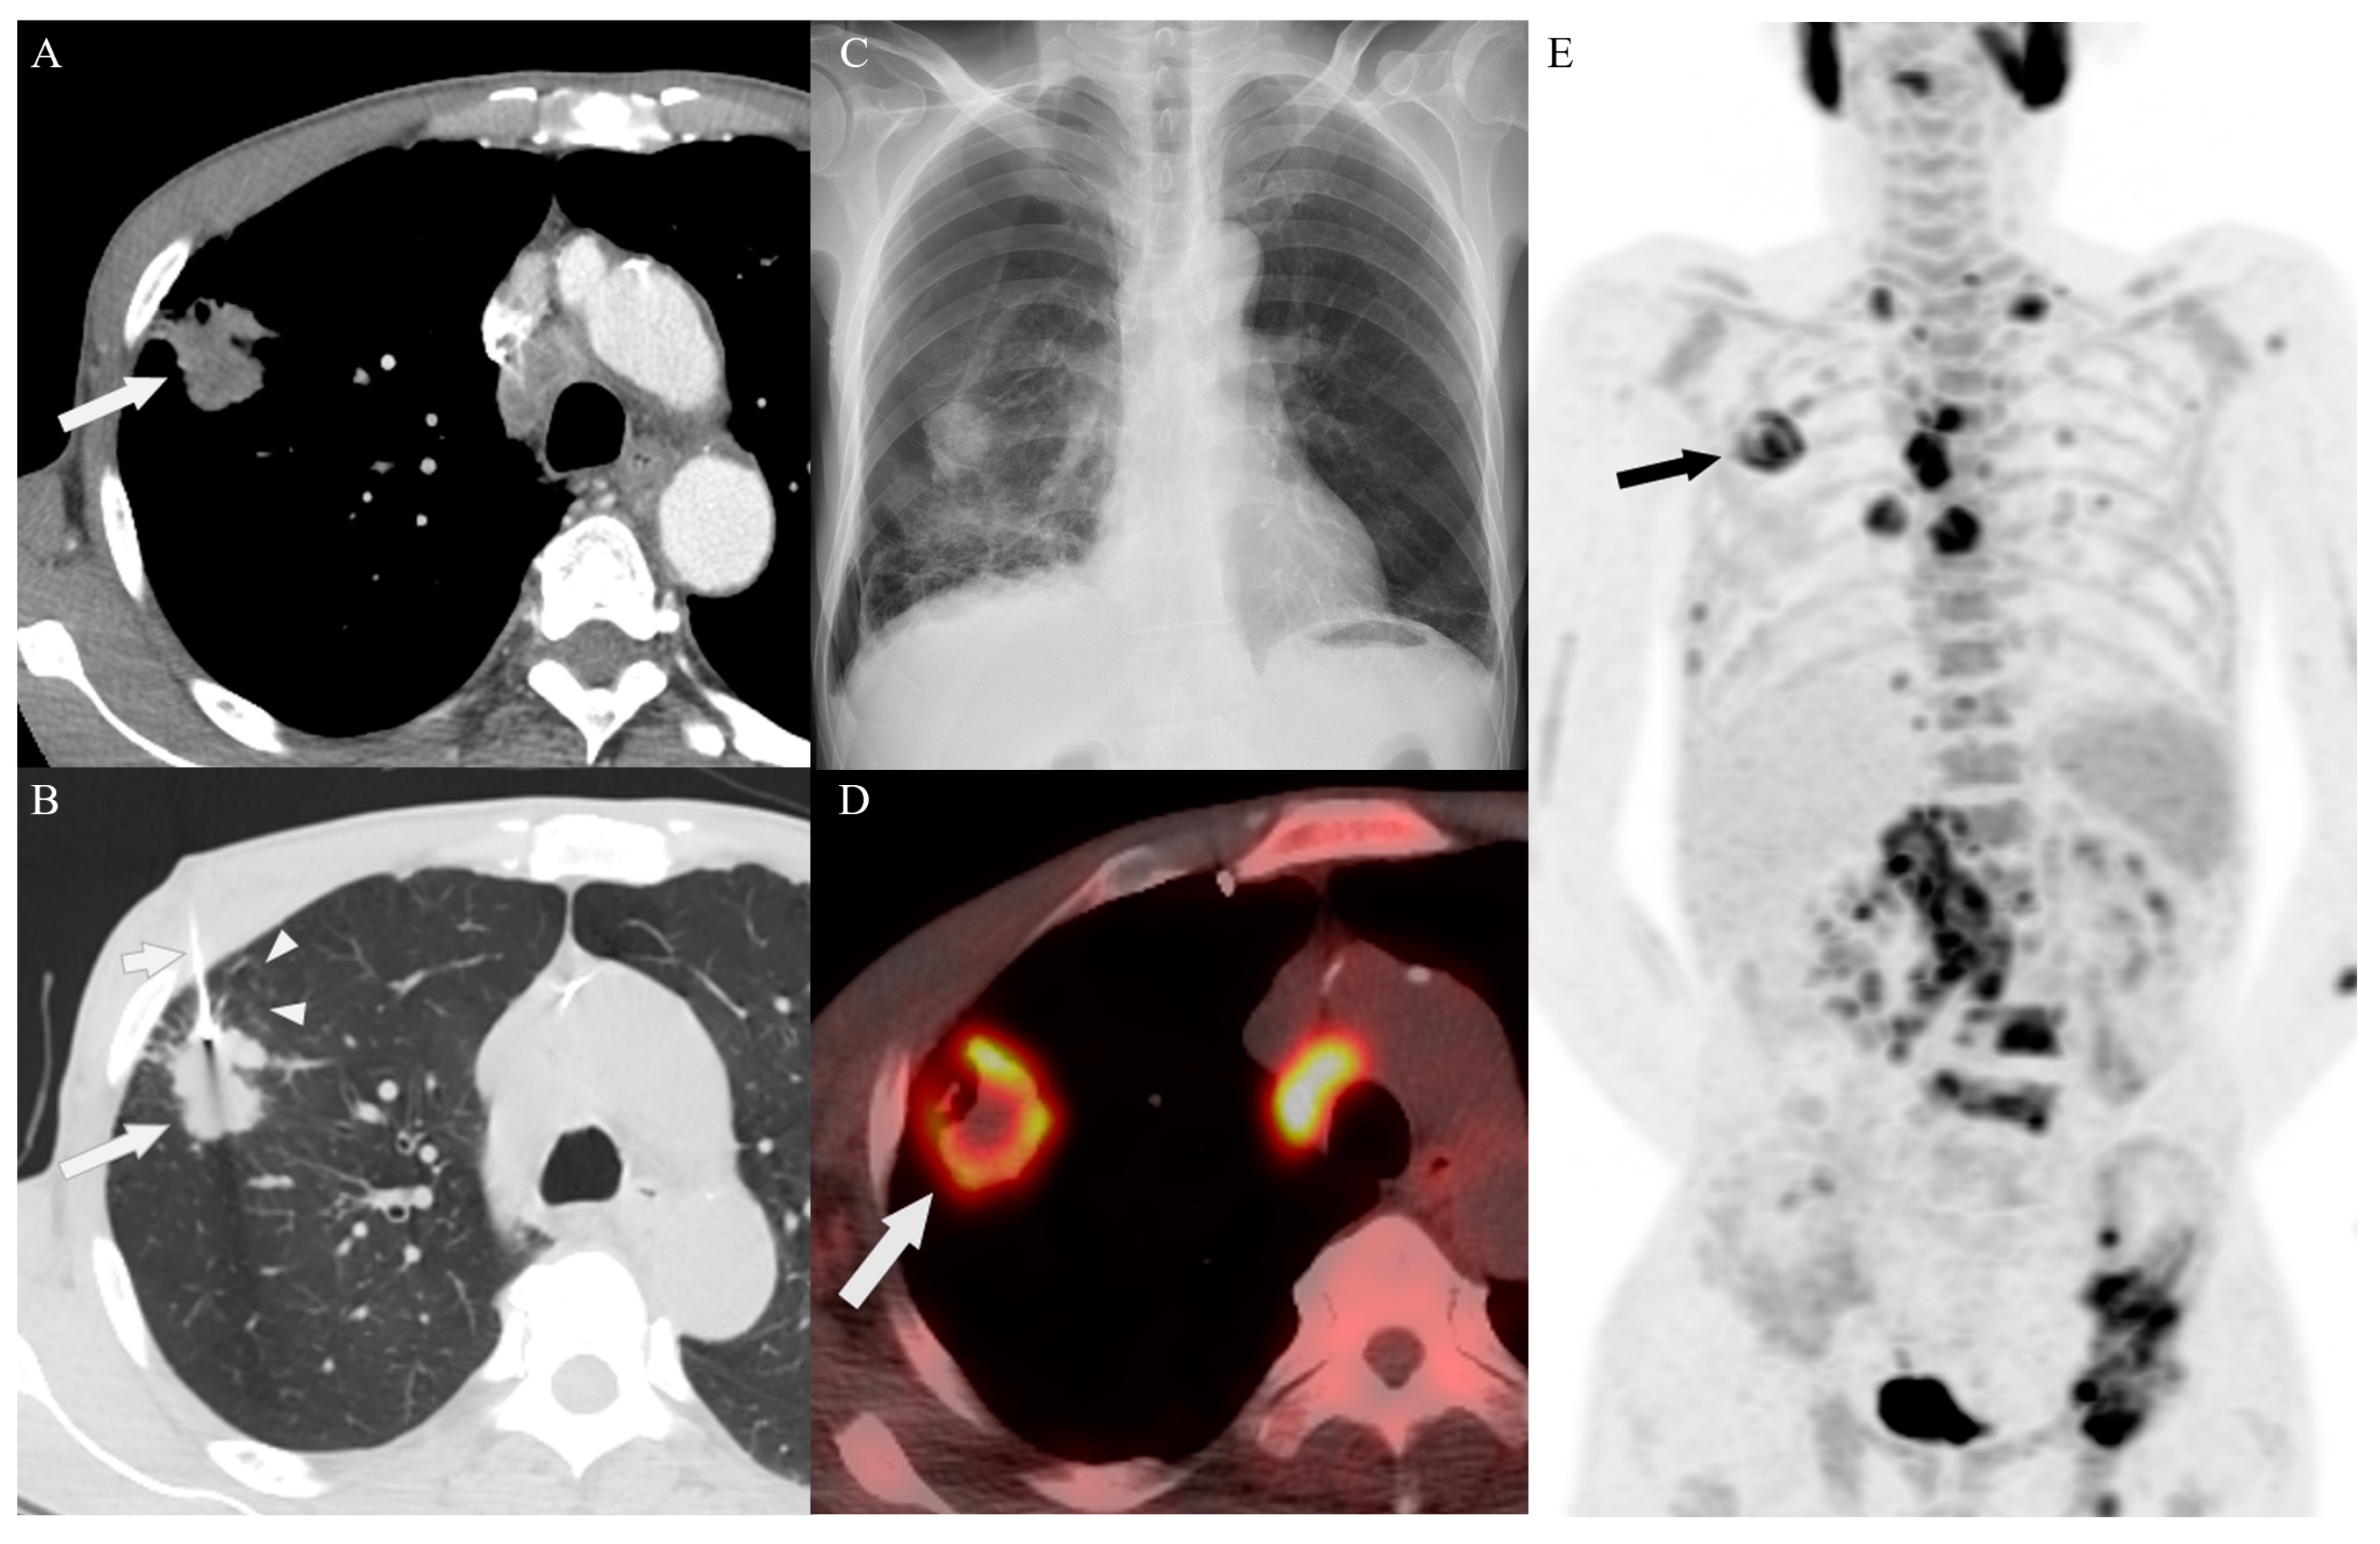

3.2. Biopsy Characteristics and Outcomes

3.4. Target Site Selection, Complications, and Diagnostic Yield According to PET/CT Timing